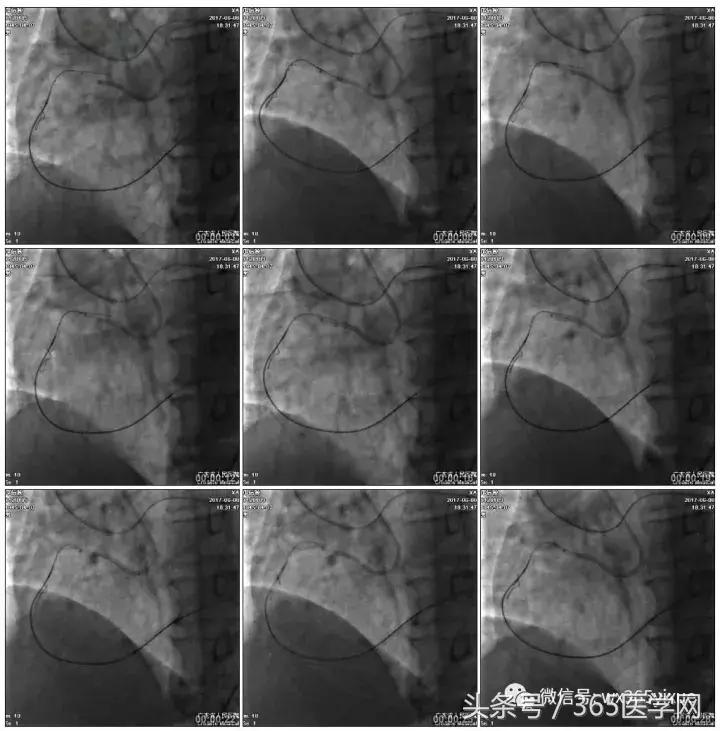

2.5*15mm球囊扩张,逆向导丝尝试,但未能进入正向GC

1.正向2.5*15mm球囊扩张,Reverse CART

2.Guidezilla延长导管辅助下,逆向导丝进入正向GC

1.更换RG3导丝

2.GC送入普通导丝,保护LM